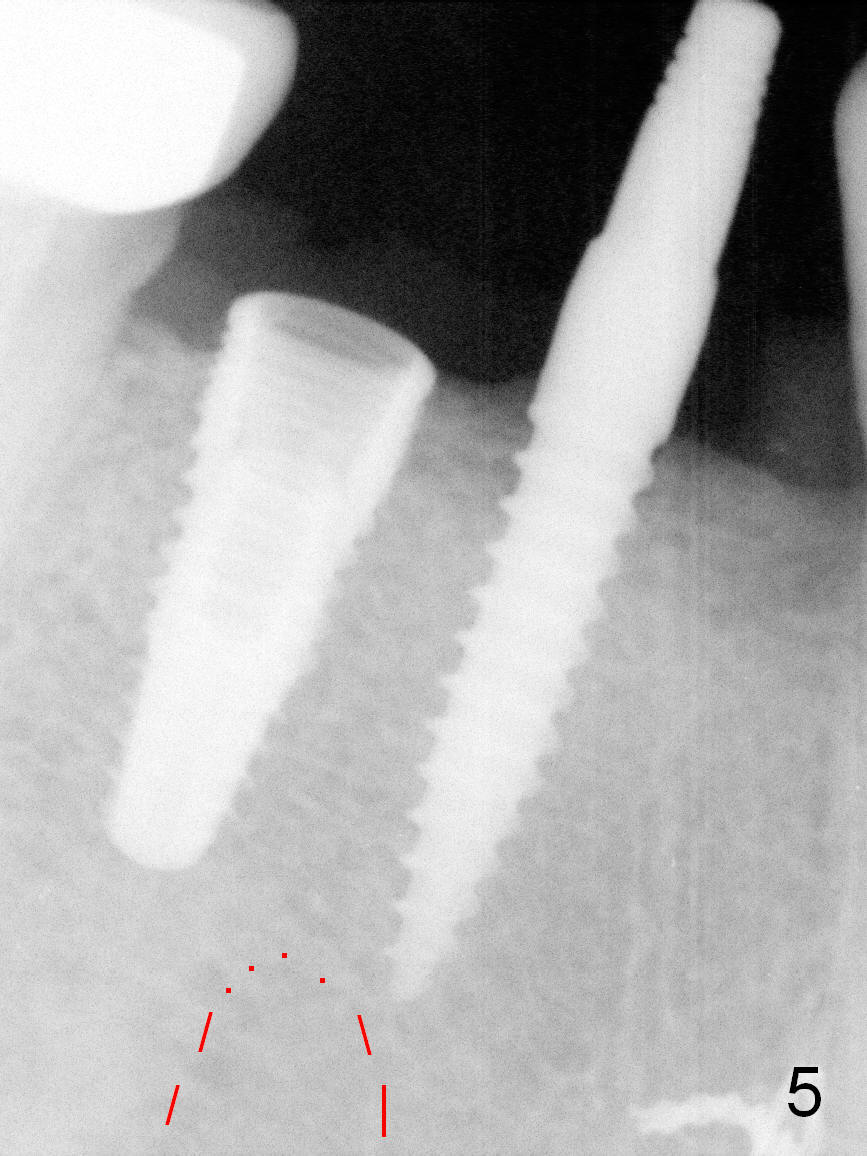

The 1st intraop PA taken after initial osteotomy at the depth of 12 mm shows that the mental loop (Fig.4 red dashed line) appears to be more superior than what is expected from CBCT study; while the apical end of the osteotomy at #28 is going to be moved mesially (>), that at #29 distally (<). Both implants (3x14 and 4.5x12 mm) are placed with insertion torque 56 Ncm (Fig.5). After placement of a 5.8x4(2) mm abutment at #29, an immediate provisional is fabricated and cemented (Fig.6 P). The partial is modified and the left portion is seated (Fig.6 <). The patient is pleased with the change: from removable to fixed appliance. There is no paresthesia postop.